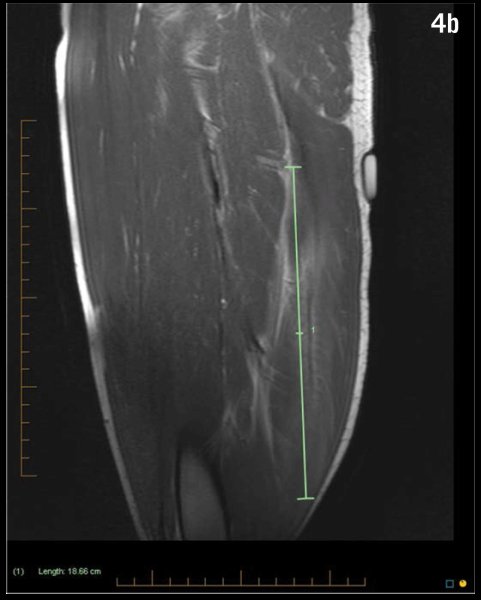

لتشخيص التمزقات العضلية 👨🏽‍⚕️📝📸

الفحص السريري Physical examination

الرنين المغناطيسي MRI

اشعة الموجات الفوق صوتية Ultrasound